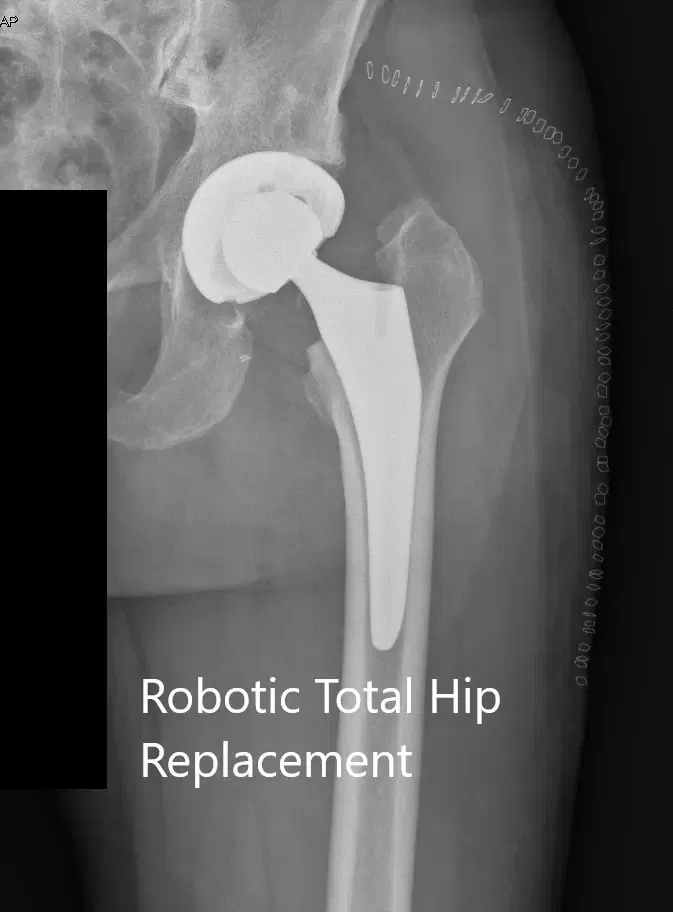

OPERATION: Robotic left total hip arthroplasty.

IMPLANTS USED: Acetabular shell 62 mm with 10-degree poly 36 mm with 127-degree neck stem size 6 with a ceramic head, 36-mm +O.

Postoperative X-ray of the left hip showing the AP and lateral views.